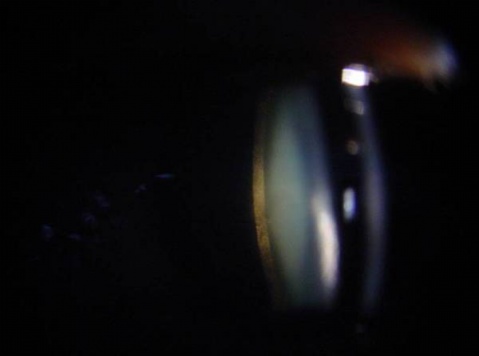

3.后囊膜下白内障(subcapsular cataract)

后囊膜下浅层皮质出现棕黄色混浊,为许多致密小点组成,其中有小空泡和结晶样颗粒,外观似锅巴状。由于混浊位于视轴,所以早期出现明显视力障碍。此类白内障进展缓慢,后期合并晶状体皮质和核混浊,最后发展为成熟期白内障。